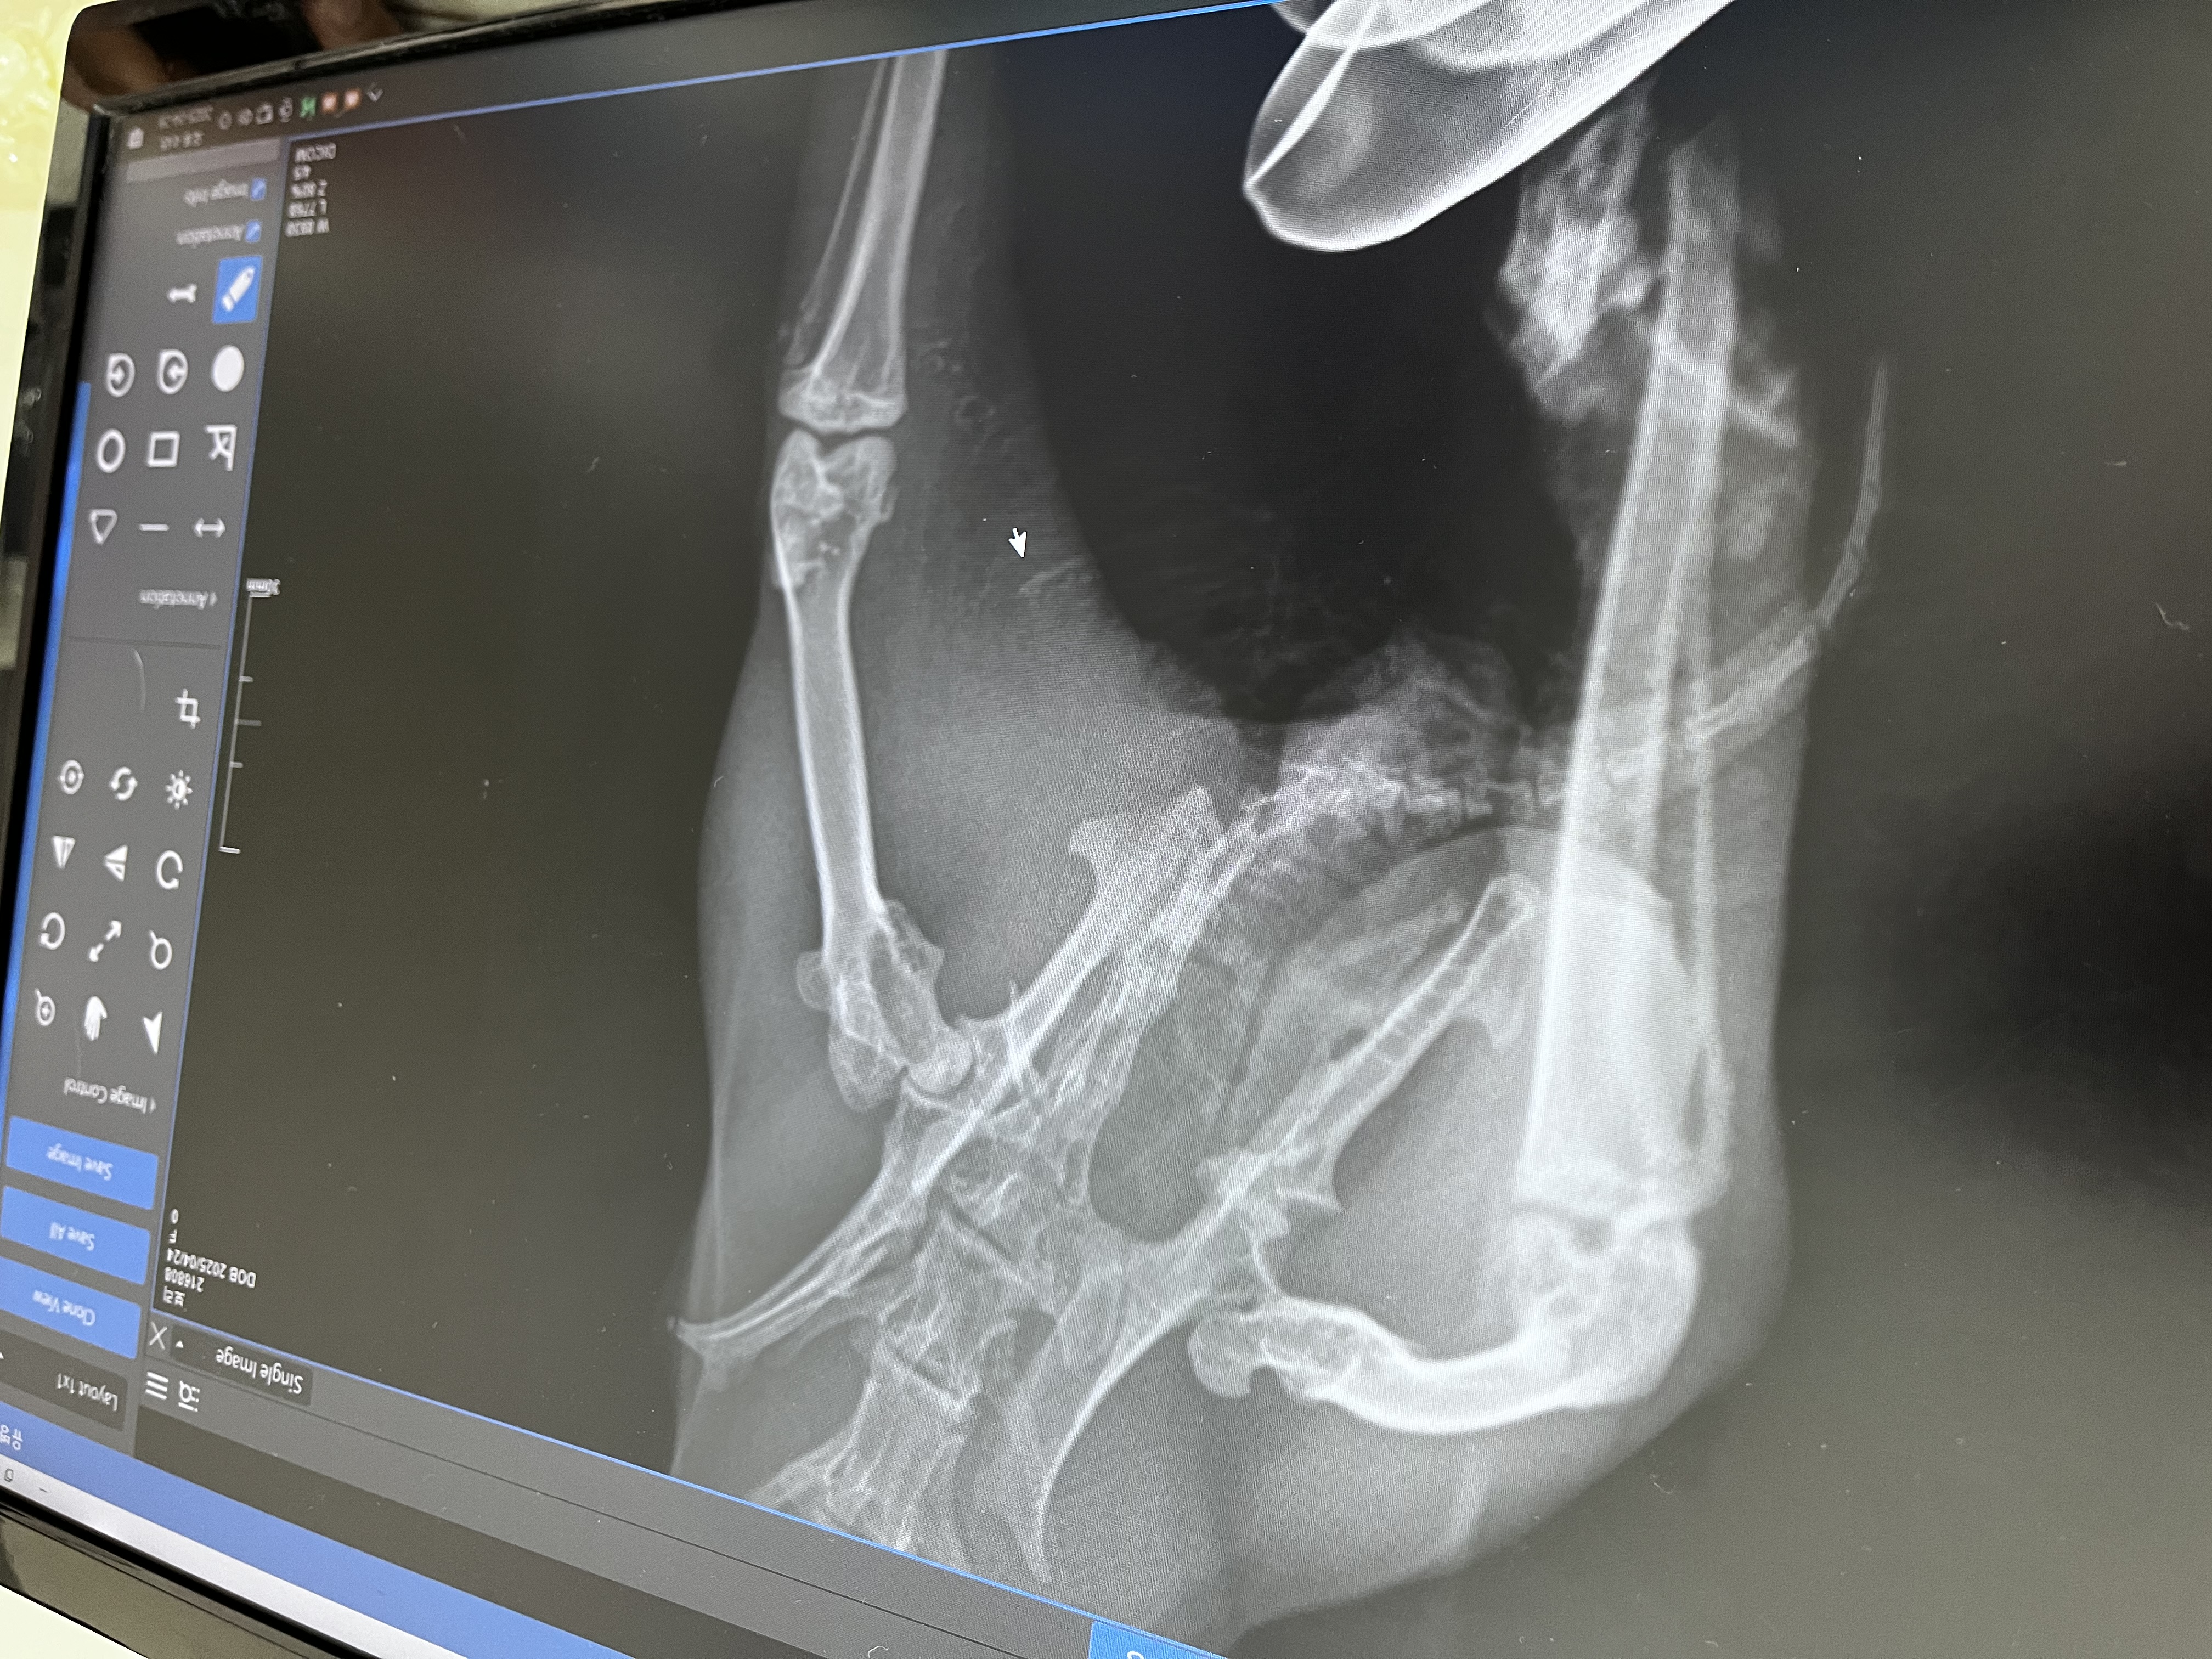

보리가 레이동물병원에서 진료받는 모습이에요!

개방창 골절 확인 및 엑스레이 사진입니다!